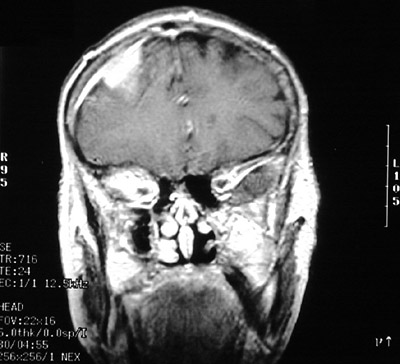

| This MRI scan in coronal views above and below demonstrates bright enhancement of a meningioma in the parasagittal region over frontal lobe. This patient only had headaches. Meningiomas grow slowly and are rarely associated with herniation. In the view below there is tailing of the meningioma into adjacent dura. |